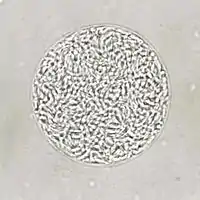

T. gondii oocysts in a fecal flotation

Feline shedding of oocysts

Infected epithelial cells eventually rupture and release oocysts into the intestinal lumen, whereupon they are shed in the cat's feces.[4]:22 Oocysts can then spread to soil, water, food, or anything potentially contaminated with the feces. Highly resilient, oocysts can survive and remain infective for many months in cold and dry climates.[29]